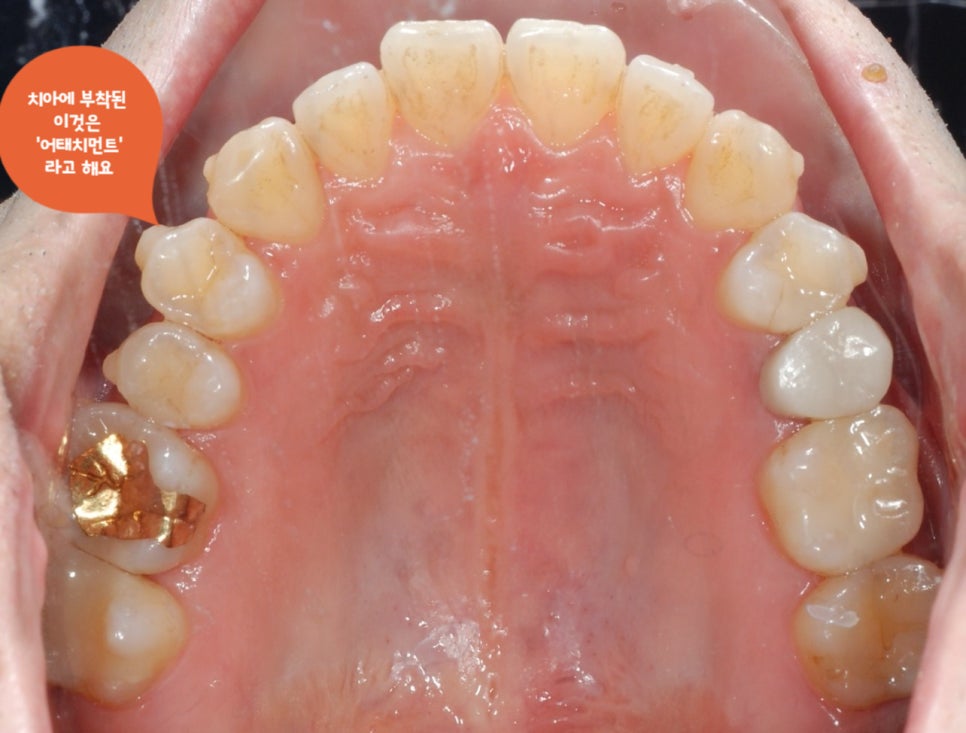

먼저

아래의 사진을 보시면

치아 표면에 쌀알처럼 붙어있는

것은 무엇일까요??

어태치먼트란

보통 충치를 때우는 레진을 치아에 부착해서

치아의 이동을 원하는 위치로

올바르게

배열시켜 주는

인비절라인에서 없어서는 안될

필수 요소입니다.

치아의 회전이나, 이동, 높이, 각도 등을

조절할 수 있는 장치이므로

잠실인비절라인에서 어태치먼트의 역할은

매우 중요합니다.

하단의

오른쪽 사진을 보시면

치아에 부탁된

어태치먼트를 확인하실 수 있습니다 :)